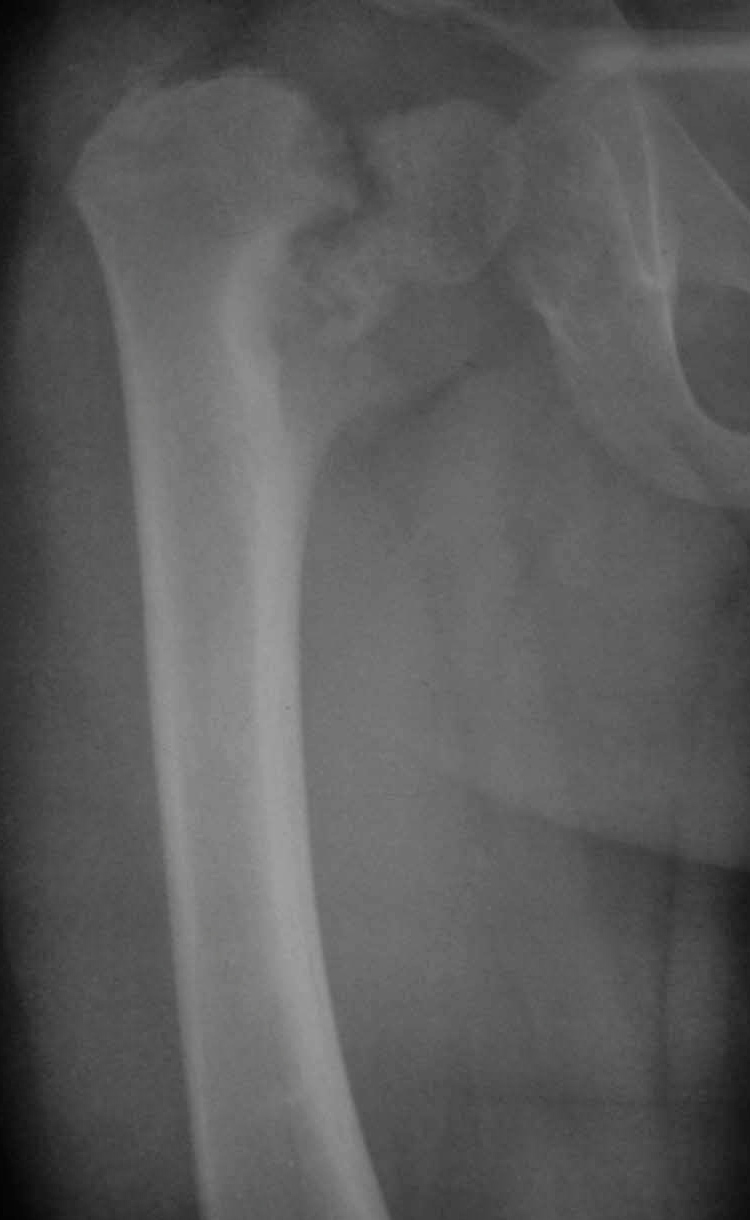

Нет, травмы в данном случае не было. Имеет место дистрофическая coxa vara, вероятнее всего, врождённаяю. Эпифизеолиз головки, который мы видим на снимке, как мы считаем, наступил вследствие нарушений биомеханики в суставе - ШДУ практически 90 градусов. Добавлю, что факт травмы родители категорически отрицают. Ребёнок постепенно начал хромать, хромата усиливалась на протяжении 6 месяцев.